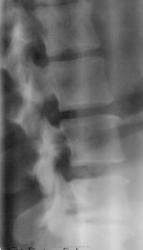

Представляю снимки моей 36-летней санитарки. Боли в спине, отдающие в таз, ноги. В прошлом была травма ( упала с высоты на спину). Расходилась, ни к кому не обращалась.

- субхондральный склероз смежных замыкательных пластиной на уровне L3-L4, L4-L5, выраженный L5-S1.

- снижение высоты межпозвонковых сегментов на уровне L3-L4, L4-L5, значительно L5-S1.

- сглаженность передне-верхних краев тел поясничных позвонков L4, L5.

- деформирующий спондилоартроз межпозвонковых суставов на уровне L3-L4, L4-L5, L5-S1.

Заключение: Остеохондроз поясничных межпозвонковых сегментов L3-L4, L4-L5 2 период, L5-S1 2-3 период(по Осна). Деформирующий спондилоартроз межпозвонковых суставов на уровне L3-L4, L4-L5, L5-S1.

Не вижу никакого соскальзывания. Диск L5-S1 конечно проблемный, резко снижен, подвижность в сегменте значительно ограничена. Если есть неврологичсеская симптоматика, надо делать МРТ.

Если проанализировать, представленную коллегой боковую рентгенограмму поясничного отдела позвоночника, то четко видно "клиновидность" суставной щели в дугоотросчатом (правда, некоторые называют по -другому) суставе, в сегменте Л4-Л5. Что - это? Судить не берусь.